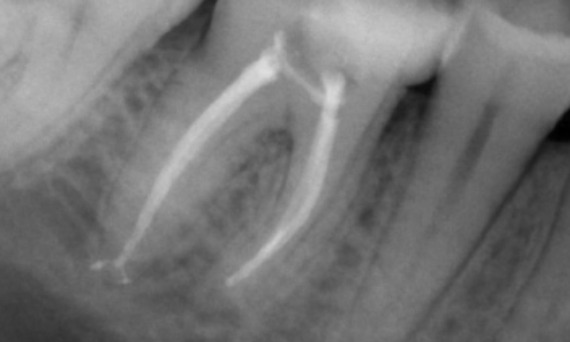

Antes: Radiolucencia periapical asociada principalmente con la raíz distal y pérdida de la lámina dura en la raíz mesial.

Después: En este caso, se eligió TruNatomy para permitir un enfoque apalancado en las caries y un enfoque en la conservación de la dentina pericervical, especialmente en el aspecto mesial donde el diente tuvo una restauración más mínima.